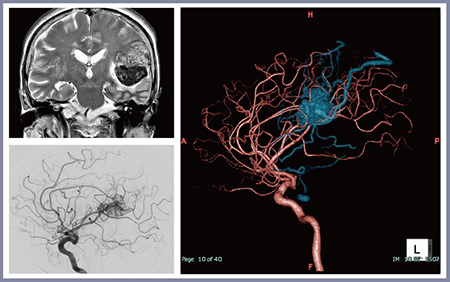

高精細CTによる症例を提示する。症例1(図1)は20歳代,男性で,左前頭葉運動野のAVM(a,b→)である。骨透過イメージ(図1 c)では全体構造が把握できるとともに,開頭やアプローチ,髄液排出部位を想定することができる。流入血管イメージ(図1 d)では,血管を色分けして表示し,どの血管から流入しているかが一目でわかるようにしている。脳や異常血管塊(nidus),流出静脈を透過することで流入血管を抽出でき,実際の術野はおおむねプランニング画像どおりで安全に手術を終了できた。

治療戦略においても,3D CTAは重要な役割を担っている。近年,術前塞栓術が増加しており,自験例でも2015年以降は70%の症例で術前塞栓術を施行している。術前塞栓術が可能かの評価も3D CTAに課せられた役割の一つである。症例2(図2)は60歳代,女性で,出血発症の左頭頂葉のAVMである。高精細CTによる3D CTAでは,流入血管がnidusをパッシングして(passing artery)正常脳へ向かう様子が明瞭に描出され,塞栓術なしで手術を行った。

図1 症例1:左前頭葉運動野のAVM

図2 症例2:左頭頂葉のAVM